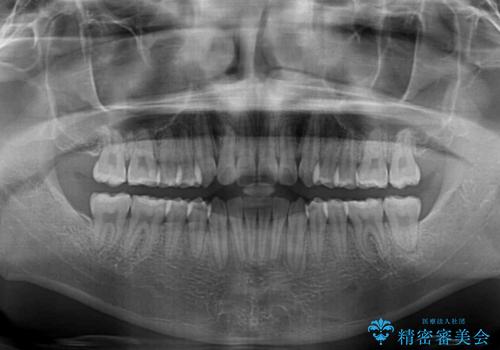

- 上下前歯のデコボコを気にして来院された患者様です。

インビザラインによる上下歯列の拡大と、IPR(歯と歯の間を削る)にるスペースの獲得により、前歯のデコボコと狭い歯列を改善することとしました。

比較的軽度な歯列不正であったため、治療期間はそれほど長くはならないと予想されました。

また、仕上がりの歯列にも若干の叢生が残ってしまいました。